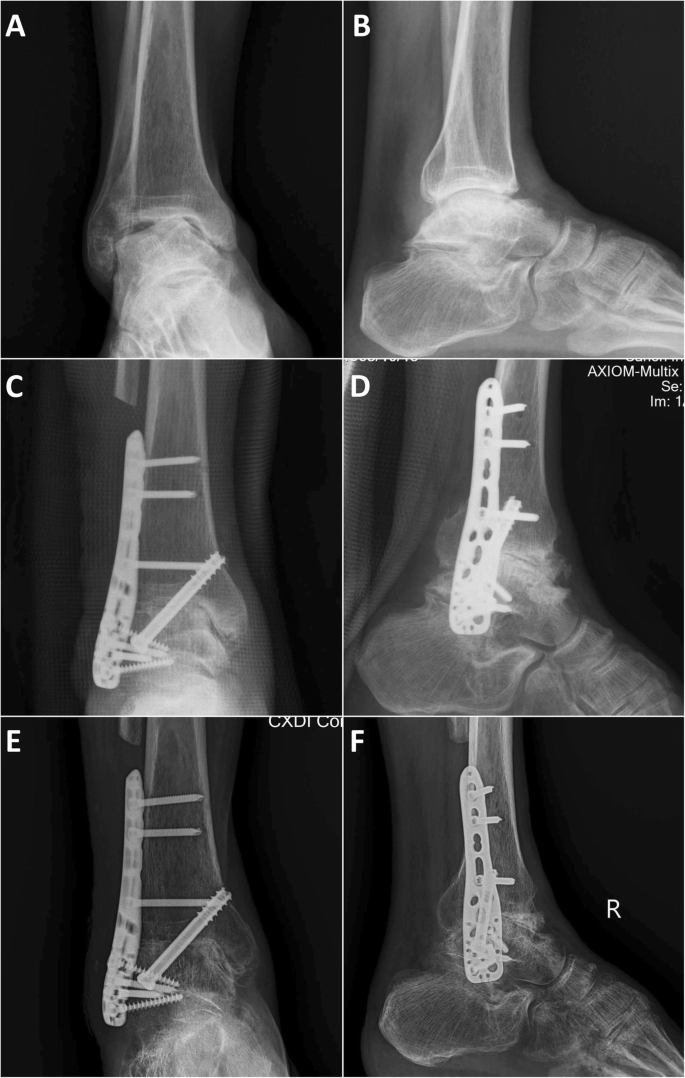

A typical case of COO subgroup, male, 49 years, the patient had a history of talus fractures 10 years ago, and followed by aseptic necrosis talus with ankle arthritis for 5 years. a, b Anteroposterior and lateral X-ray film 3 days before operation, we can found that the talus was severely varus and collapsed, and was hardened with a lot of sequestrum. c, d Anteroposterior and lateral X-ray film 3 days after operation; we made distal fibular osteotomy and large lesion cleaning, the distal fibula was separated and crushed, for impacted and structural bone grafting, the joint space was filled and pressurized. e, f Anteroposterior and lateral X-ray film 3 months after operation; no obvious internal fixation loosening was observed, and a small number of bone bridges were found in the joint space. However, the ankle fusion was not ideal at this point, and the patient had been found a good fusion 6 months after operation

Through postoperative imaging examination, all groups can be found the joint space were filled and pressurized (Figs. 1, 2, and 3) The surgical time of SOO subgroup (123.6 ± 18.6 min) was significantly less than the AAF group (140.5 ± 22.2 min) (P = 0.046) and COO subgroup (149.3 ± 23.1 min) (P = 0.006). The intra-op blood loss of AAF group (137.1 ± 49.7 ml) was significantly less than the OAF group (184.6 ± 62.9 ml) (P = 0.012) and the COO subgroup (206.7 ± 67.8 ml) (P = 0.002), and the intra-op blood loss of SOO subgroup (154.5 ± 41.6 ml) was significantly less than the COO subgroup (206.7 ± 67.8 ml) (P = 0.034). The reduction of ALB (the difference of albumin value between preoperative 2 days and postoperative 2 days) (1.28 ±0.28 g/L) of AAF group was significantly less than the OAF group (3.35 ± 1.19 g/L) (P = 0.000), the COO subgroup (3.49 ± 1.22 g/L) (P = 0.000), and the SOO subgroup (3.15 ± 1.19 g/L) (P = 0.000). Similarly, the total hospital stays of AAF group (6.3 ± 2.5 days) was significantly less than the OAF group (11.0 ± 2.7 days) (P = 0.000), the COO subgroup (11.4 ± 3.4 days) (P = 0.000), and the SOO subgroup (10.5 ±1.5 days) (P = 0.000). One patient of AAF group, two patients of COO subgroup, and one patient of SOO subgroup had transient paralysis of nerve after operation; three patients of COO subgroup and one patient of SOO subgroup had delayed wound healing after operation; and one patient of COO subgroup had soft tissue infection after operation (Table 3, Fig. 4).

At 3 months after operation, no obvious internal fixation loosening were observed in all groups; for most of the AAF group and SOO subgroup patients, we can find a lot of bone bridges in the joint space, and the ankle fusion were ideal; but there were only a part of patients in COO subgroup can be found ideal ankle fusion (Fig. 1, 2, and 3) The union time of AAF group (12.4 ± 1.9 weeks) was significantly less than the OAF group (14.6 ± 3.4 weeks) (P = 0.019) and the COO subgroup (15.5 ± 3.5 weeks) (P = 0.003), and the union time of SOO subgroup (12.8 ± 2.3 weeks) was significantly less than the COO subgroup (15.5 ± 3.5 weeks) (P = 0.035). In COO subgroup, there were two cases that had non-fusion after primary ankle fusion surgical; both of them underwent refusion revision surgery (Table 3, Fig. 4).